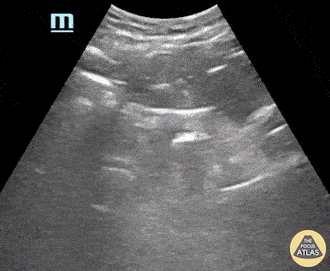

An elderly male with a history of atrial fibrillation, hypertension, and COPD presented for evaluation of lower abdominal pain. He denied associated fever, chills, nausea, vomiting, dysuria, increased urinary frequency, hematuria, or incontinence. Also denied history of smoking or exposure to aniline dyes. POCUS was notable for the presence of a hyperechoic mass along the posterior wall of his urinary bladder. This prompted additional image acquisition; CT confirmed the presence of a 2.8 x 1.6 x 3.6 cm bladder mass warranting additional work-up. This serves as an example of how POCUS can help localize intra-abdominal areas of interest, particularly in the setting of a vague HPI. Thomas G. Weiss, MS4; Matthew French, PGY3 Central Michigan University College of Medicine